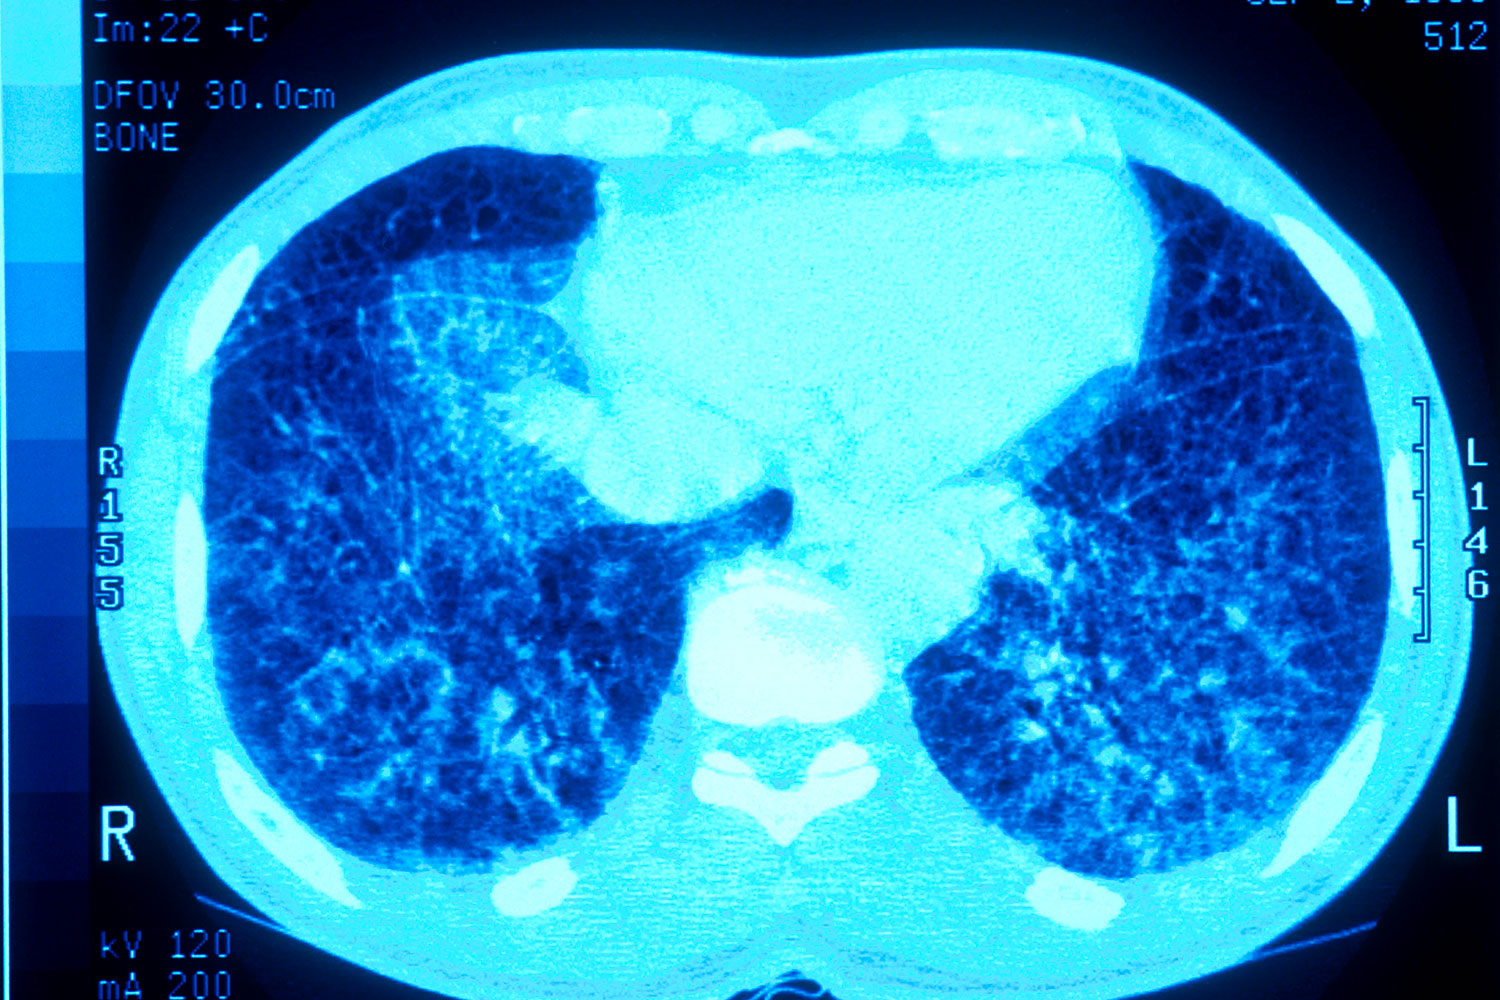

Según señala Luis Martí-Bonmatí, ex presidente de la SERAM, académico de Número de la Real Academia de Medicina de España y director de área clínica de Imagen Médica del Hospital Universitario y Politécnico La Fe de Valencia, "la IA ha irrumpido con fuerza en la radiología abdominal prometiendo una transformación profunda: detección más ágil, flujos de trabajo optimizados y una mejora global en la calidad diagnóstica". Sin embargo, pese a sus avances técnicos y unos beneficios que parecen tan claros en la mejora de la eficiencia, precisión y estandarización de los informes radiológicos, "su adopción en la práctica asistencial diaria sigue estando limitada" por barreras tecnológicas, metodológicas y de integración de los propios profesionales en los circuitos.  En su opinión, "si los radiólogos no participan realmente en la toma de decisiones, si no se armonizan los criterios de evaluación tecnológica y clínica, los modelos que se implementen no serán robustos ni lograrán resultados clínicamente fiables y generalizables".

Para el especialista, la IA ofrece ventajas en la reducción de tiempos de informe, aumento de la sensibilidad diagnóstica, mejora de su reproducibilidad, reduciendo la variabilidad interobservador, y estandarización del proceso radiológico, desde la adquisición hasta el informe final. En oncología, donde el seguimiento mediante imagen es un pilar fundamental, "estas capacidades son especialmente relevantes". La IA permite una evaluación longitudinal, multimodal y multiorgánica, mejorando la monitorización de la progresión tumoral y la respuesta al tratamiento. Por todo ello, expone, "existen ya múltiples escenarios donde la IA está demostrando valor: esteatosis hepática (cuantificación automática y reproducible), carcinoma hepatocelular (caracterización), cáncer de próstata (segmentación glandular y mejora en la detección de lesiones clínicamente significativas) y evaluación de respuesta tumoral (RECIST, mediciones automáticas y seguimiento longitudinal)". La IA aplicada a la radiómica añade variables como textura, realce o cambios en el tiempo (delta-radiomics), "ampliando la evaluación más allá del tamaño tumoral".